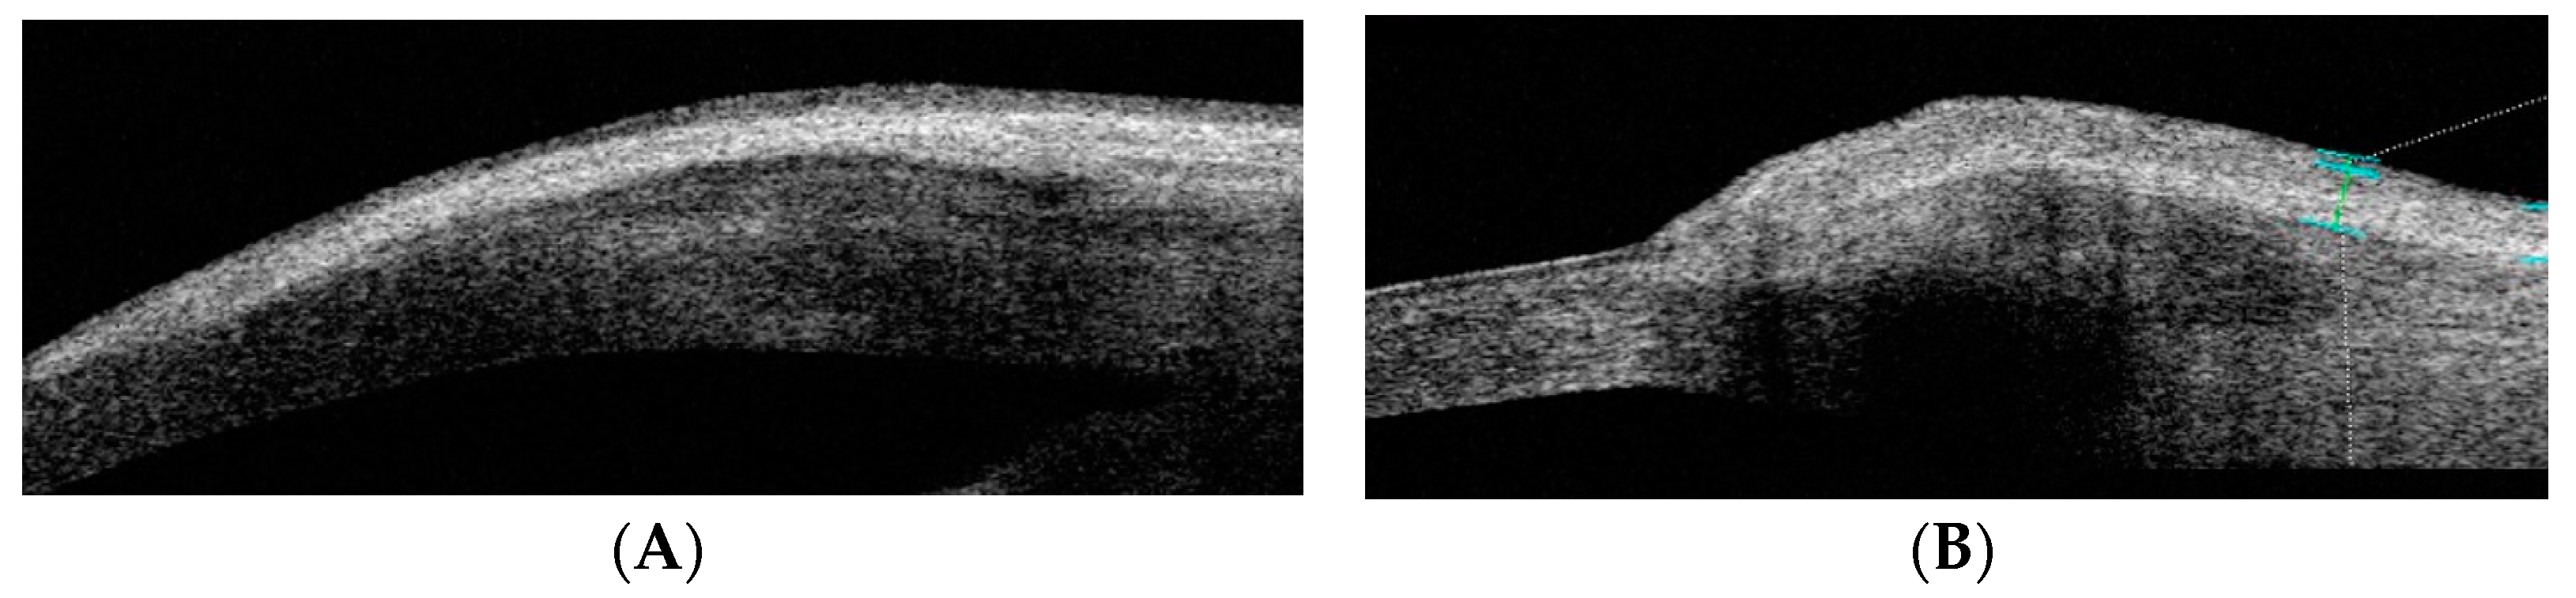

Measurements of anatomical characteristics using AS-OCT were made in the horizontal meridian at the center of the pterygium as follows (as described in previous studies) (Figure 2 and Figure 3) [6]:

• Drawing a line perpendicular to the ocular surface at the scleral spur level.

• The intersection of this line with the ocular surface is the reference point from which measurements were taken towards the cornea or towards the bulbar conjunctiva or graft.

Figure 2. AS-OCT image illustrating the measurement of corneal invasion. The reference point is taken by drawing a line perpendicular to the ocular surface starting at the scleral spur.

Figure 3. AS-OCT image illustrating measurements taken towards the conjunctiva at 1, 2, and 3 millimeters from the reference point.